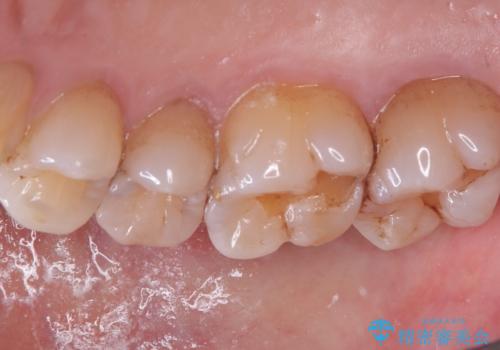

右上5番の近遠心にう蝕が認められたため、CR裏層の後MOD窩洞のセラミックインレーとしました。

インレーセット時はラバーダム防湿を行っています。